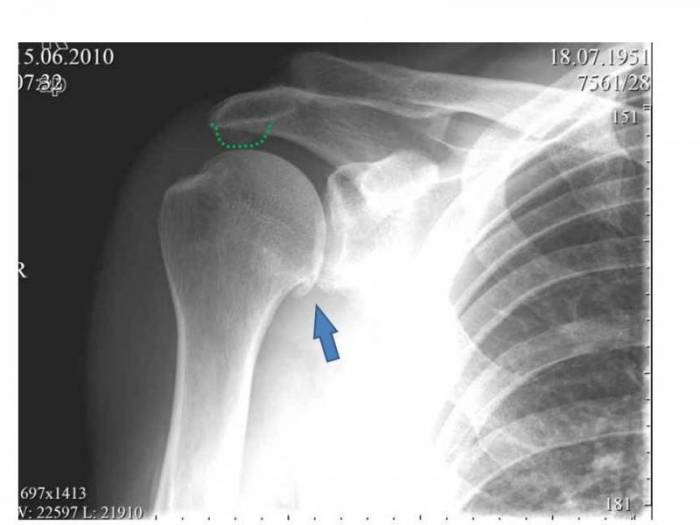

Рентгенография

Необходима для визуализации костных структур плечевого сустава. С помощью рентгенологического исследования врачи оценивают состояние клювовидно-акромиальной связки, акромиально-ключичного сустава и плечелопаточного соединения. При импиджменте специалисты выявляют децентрацию головки плечевой кости, патологические изменения большого бугорка, оссификацию связок и признаки артроза плечевого сустава.